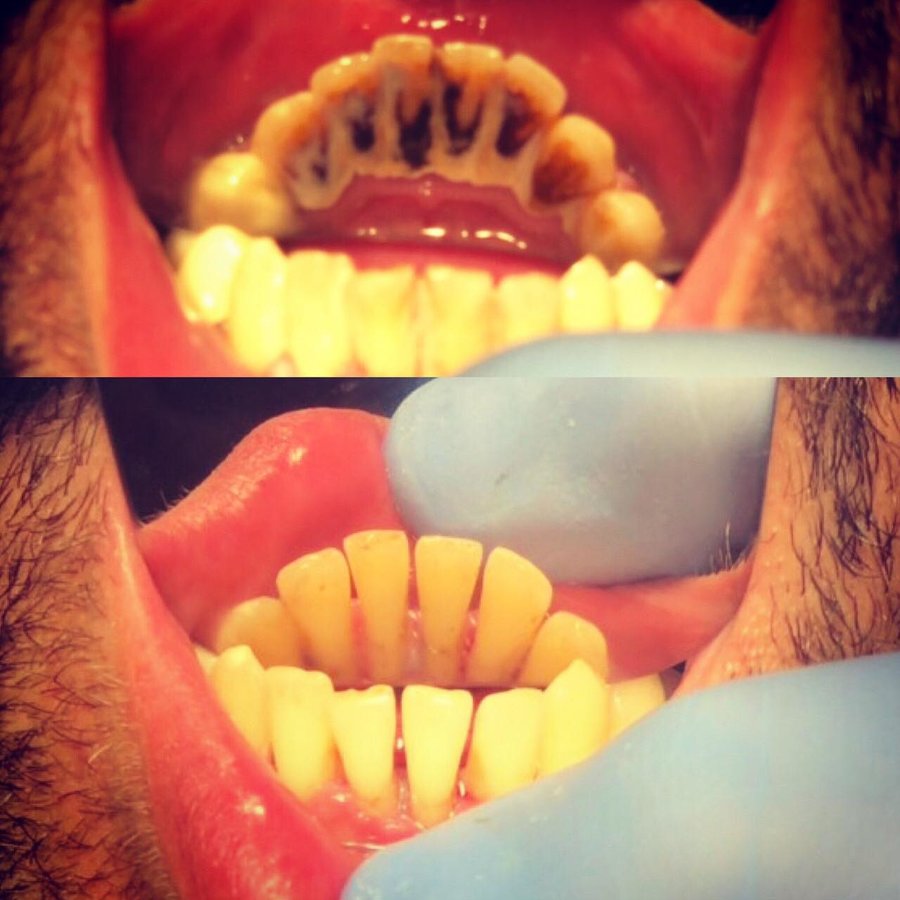

Dental Braces $2783

Child Dental Braces $2783

Sinus Treatment $2783